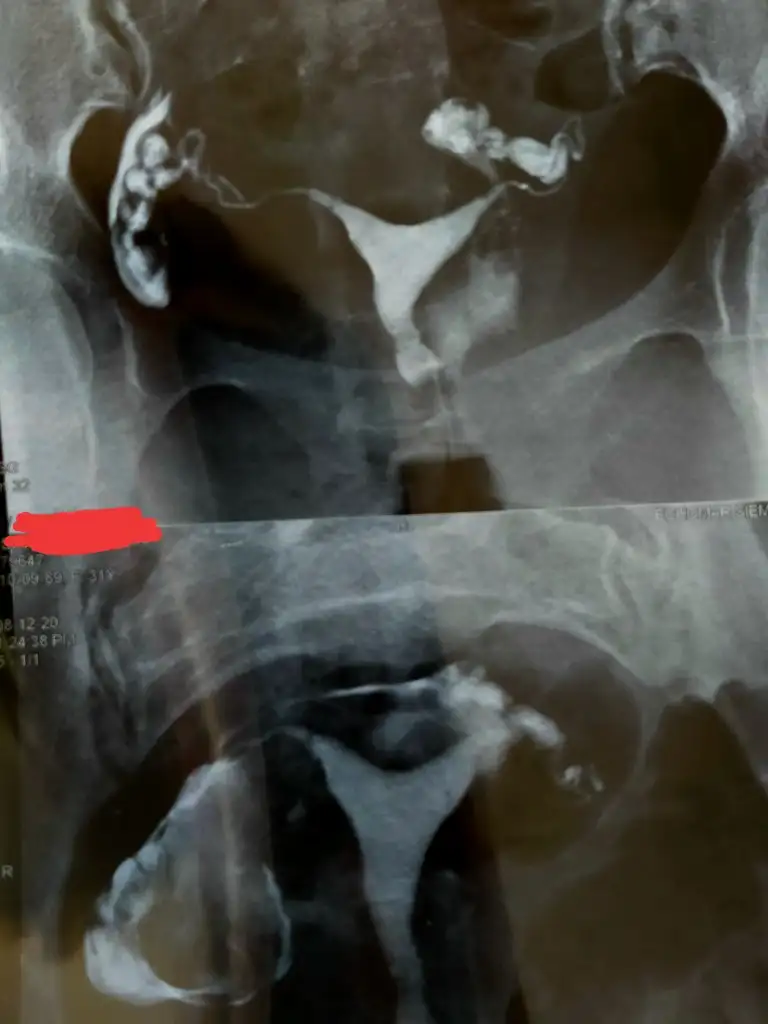

Sizin ki tam t benim y şeklinde birazBen t şeklindeydi birde üstten de basıklık vardı

Evet senin daha geniş gibi görülüyor içi sen yinede tek bir doktora bağlı kalma birkaç doktora göster benim de bazı doktorlar gerek yok dedi ama en sonunda gerek olduğu anlaşıldı o yüzden 2 yıl kaybettim ben benimde y şekline yakın dedi doktor üstten de basık yanlardan darSizin ki tam t benim y şeklinde biraz

Merhaba. Benim rahim şeklide seninkine benziyo biraz. Histeroskopi yaptırmıştım ama yinede bebeğimin kalbi durdu. kan pıhtılaşma sorunu da var bendeSizin ki tam t benim y şeklinde biraz

Aynı benimde böyle çıktı dün hsgde size ne dedi doktor

Büyük problem yaratmaz dediAynı benimde böyle çıktı dün hsgde size ne dedi doktor

Şuan tüp bebek tedavisindeyim benim filmim bu şekilde histeroskobi dedi Dr kararsizimBüyük problem yaratmaz dedi